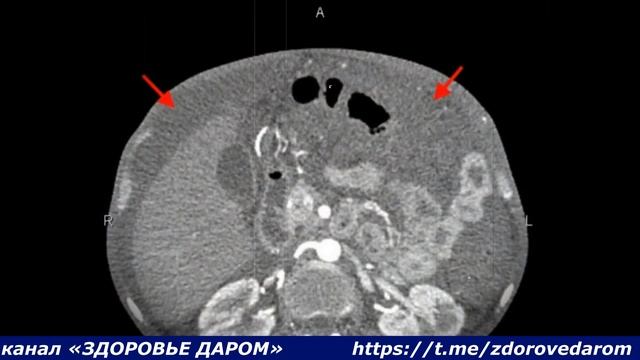

Подписывайтесь на канал и ставьте лайки, если понравилось видео. Заранее спасибо❤❤😍 * --------------------------------------------------------------------------------------------------------------------- --------------------------------------------------------------------------------------------------------------------- * Асцит (др.-греч. ἀσκίτης — водянка, от ἀσκός — мех для хранения жидкости), брюшная водянка — скопление свободной жидкости в брюшной полости. Количество её может достигать 25 л. Асцит является следствием цирроза печени — в 75 % случаев, злокачественных новообразований — в 10 % случаев, сердечной недостаточности — в 5 % случаев. В клинической картине у пациентов отмечается увеличение объёма живота и прогрессирующее нарастание веса. * ----------------------------------------------------------------------------------------------------------------------- ----------------------------------------------------------------------------------------------------------------------- * #здоровыйчеловек #здоровье #медицина #здоровье #медицина #врач #доктор #здоровьеидолголетие #правильноепитание #здоровоепитание #здоровыйчеловек #здоровье #медицина #здоровье #медицина #врач #доктор #здоровьеидолголетие #правильноепитание #здоровоепитание #здоровыйчеловек #здоровье #медицина #здоровье #медицина #врач #доктор #здоровьеидолголетие #правильноепитание #здоровоепитание #здоровыйчеловек #здоровье #медицина #здоровье #медицина #врач #доктор #здоровьеидолголетие #правильноепитание #здоровоепитание #здоровыйчеловек #здоровье #медицина #здоровье #медицина #врач #доктор #здоровьеидолголетие #правильноепитание #здоровоепитание #здоровыйчеловек #здоровье #медицина #здоровье #медицина #врач #доктор #здоровьеидолголетие #правильноепитание #здоровоепитание #здоровыйчеловек #здоровье #медицина #здоровье #медицина #врач #доктор #здоровьеидолголетие #правильноепитание #здоровоепитание #здоровыйчеловек #здоровье #медицина #здоровье #медицина #врач #доктор #здоровьеидолголетие #правильноепитание #здоровоепитание